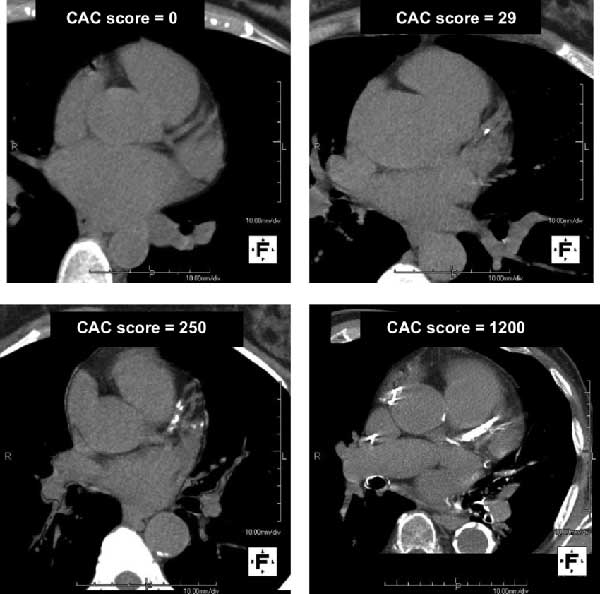

Calcification of the coronary arteries is a marker of advanced atherosclerosis.

And is an excellent marker of cardiovascular risk.

A score of 0 means there are no significant deposits of calcified atherosclerosis.

It DOES NOT mean there is no atherosclerosis.

However, with a CAC of 0 over 10 years:

- Heart attack risk is about 2-5%

- All-cause mortality risk is <2%

Therefore very low risk.